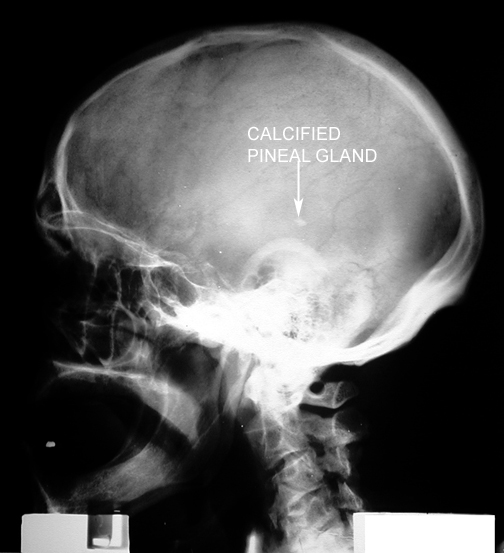

Identify the pineal body. Click the image for labeling.